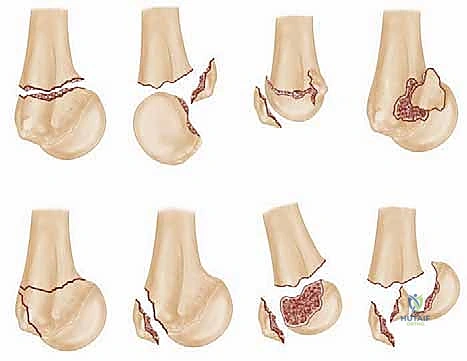

1. تصنيف نير (Neer Classification)

يُعد هذا التصنيف هو الأكثر استخداماً عالمياً. يعتمد الدكتور "نير" في تصنيفه ليس على خطوط الكسر فحسب، بل على عدد الأجزاء العظمية التي انفصلت وتحركت من مكانها الأصلي.

يُعتبر الجزء "نازحاً" (Displaced) فقط إذا تحرك مسافة 1 سم أو أكثر، أو إذا مال بزاوية 45 درجة أو أكثر عن وضعه الطبيعي. الأجزاء الأربعة التي يقيمها التصنيف هي (رأس العضد، الحدبة الكبرى، الحدبة الصغرى، جسم العضد).

- كسور الجزء الواحد (One-part fractures): بغض النظر عن عدد خطوط الكسر، إذا لم تتحرك الأجزاء عن مكانها (أقل من 1 سم وأقل من 45 درجة)، تُعتبر جزءاً واحداً. تشكل 80% من الحالات، وعلاجها غالباً تحفظي.

- كسور الجزأين (Two-part fractures): جزء واحد فقط يتحرك من مكانه (مثال: كسر وانزياح في الرقبة الجراحية فقط، أو انزياح الحدبة الكبرى فقط).

- كسور الثلاثة أجزاء (Three-part fractures): انزياح جسم العضد مع انزياح إحدى الحدبات (غالباً الكبرى). هنا يكون رأس العضد لا يزال متصلاً بالحدبة الأخرى، مما يحافظ على جزء من التروية الدموية.

- كسور الأربعة أجزاء (Four-part fractures): جميع الأجزاء الأربعة منفصلة ونازحة عن بعضها. هذا هو النوع الأخطر والأكثر تعقيداً، حيث تنقطع التروية الدموية تماماً عن رأس العضد، وتكون نسبة حدوث النخر اللاوعائي (AVN) عالية جداً. يتطلب هذا النوع مهارة جراحية استثنائية كالمتوفرة لدى الدكتور هطيف.